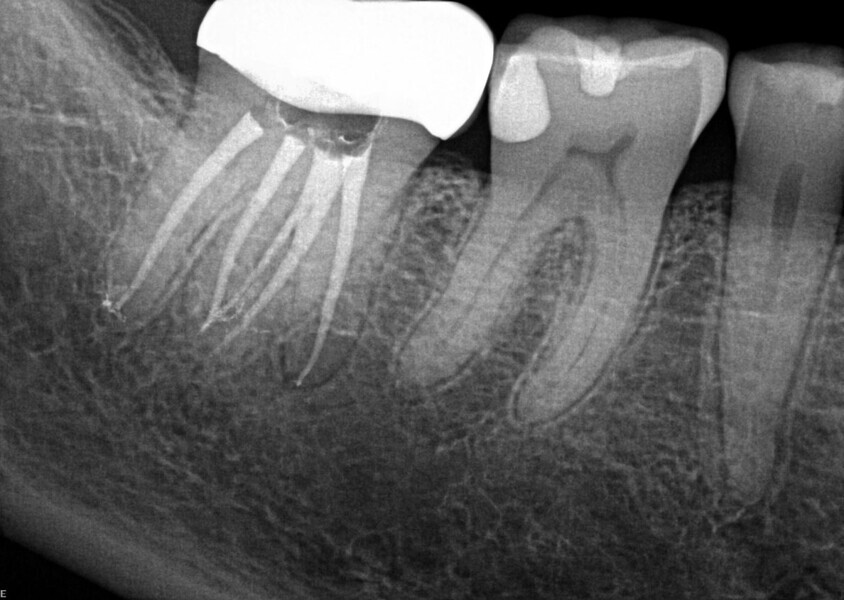

Fig. 14a: Case treated with Bassi Logic controlled memory nickel titanium files. Note the visualization of the third root on this lower molar and conservative canal preparation shape. (Courtesy of Dr. Alex Chan)

Fig. 14b: Case treated with Bassi Logic controlled memory nickel titanium files. Note the visualization of the third root on this lower molar and conservative canal preparation shape. (Courtesy of Dr. Alex Chan)